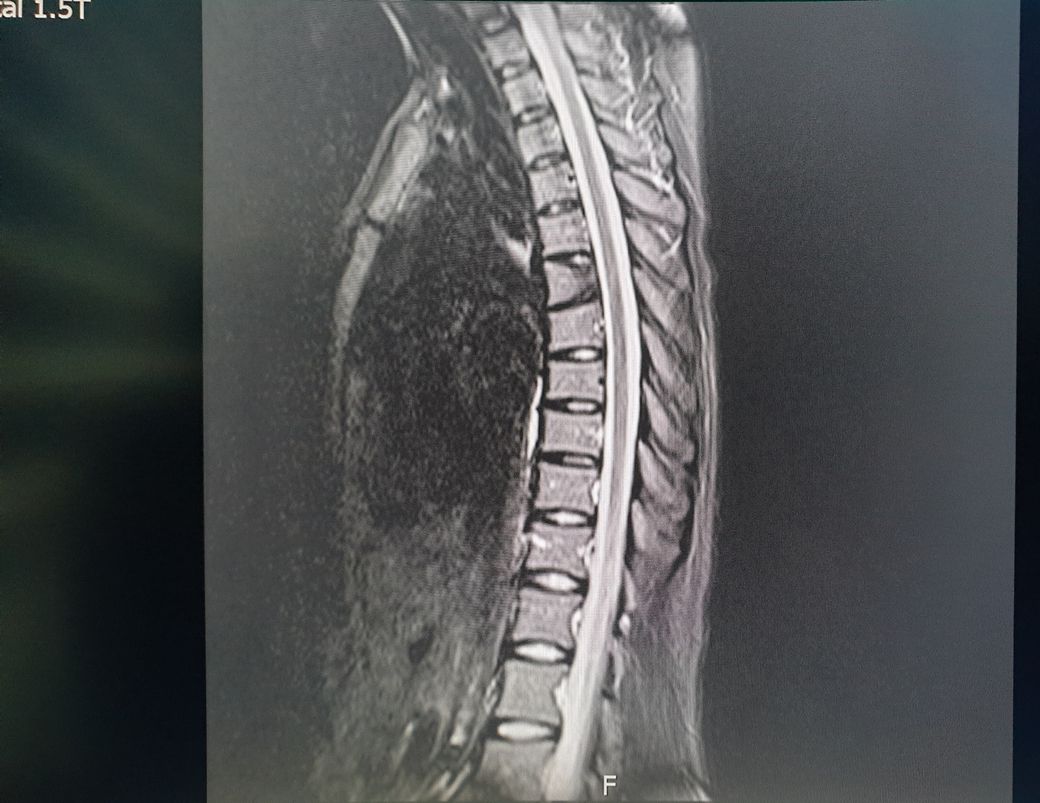

지난달 CTLmri 찍었는데 흉추뼈가 이상해서요 선생님은 괜찮다고했지만 저는 등짝부터 요추까지 그날이후로 조금만 무거운거 들어도 아프고 뻐근하거든요 괜찮은게 맞아요?

MRI는 연속적인 수백장의 사진을 봐야해서 한 장만 가지고는 말씀드리기 어렵습니다.

사진 상 이상이 있어 보이는 흉추 1개는 압박성 골절이나 선천성 기형일 수 있으나 한 장 만으로는 알 수 없습니다.